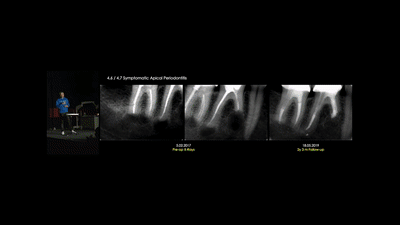

Guided endodontics treatment